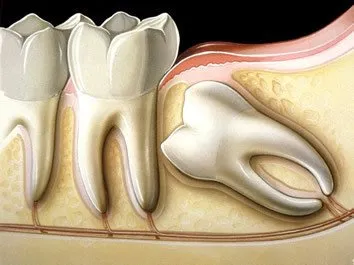

Além disso, existem casos mais complicados que necessitamos realizar uma tomografia. Nesses exames vamos examinar primeiramente a posição do siso, ele pode estar na posição "normal" ou em "pé", ou seja,como todo outro dente.

Mas, existem muitos casos, onde ele pode estar "deitado" o que dificulta muito a nossa cirurgia.